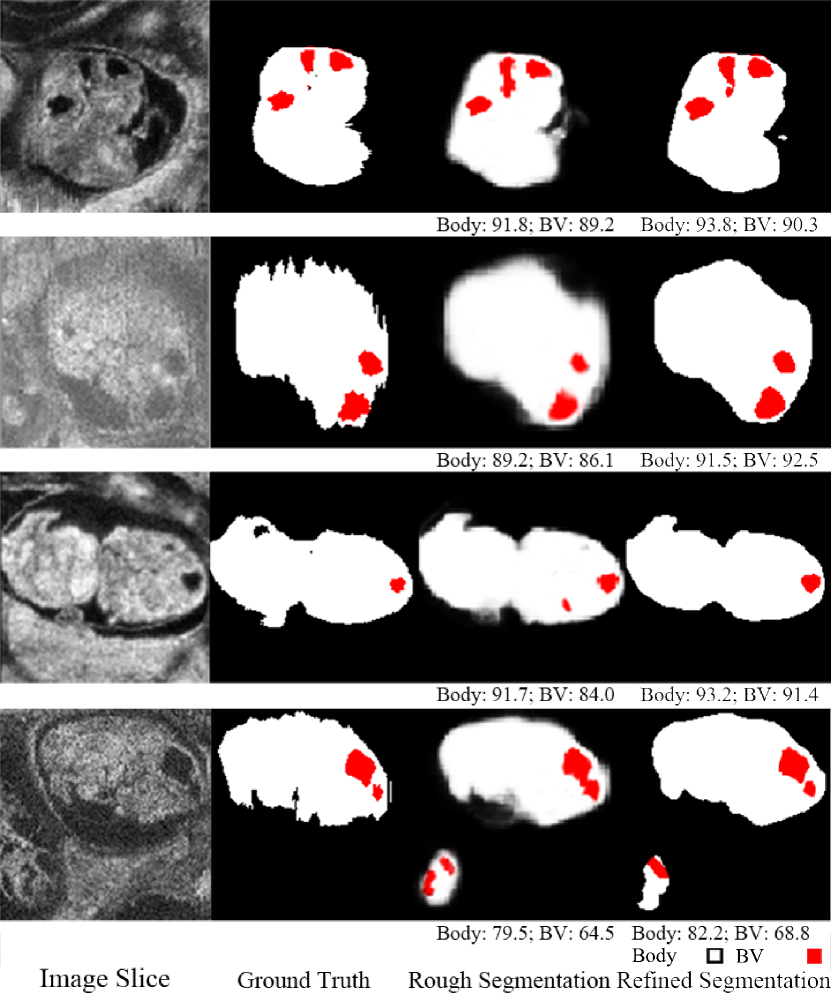

Fig. 1: An example of image data, ground truth label, initial rough segmentation and final refined segmentation. The numbers below the 3D segmentation are corresponding DSC.

Fig. 4: Qualitative segmentation results of end-to-end auto-context refinement framework for 4 ultrasound volumes. Red indicates BV, white indicates body and the numbers below the predicted segmentation are corresponding DSC. The second row is an image with motion artifacts so the ground truth is noisy in the body background boundary. The refined network produces a smooth boundary which is closer to the true physical structure. The last row is an image with one complete embryo and one partial embryo but only the complete one is labeled. The predicted label contained part of the incomplete embryo.

As shown in Fig. 4, the initial segmentation produces reasonable body segmentations along with very rough BV segmentations. After end-to-end refinement, the segmentation accuracy was substantially improved.